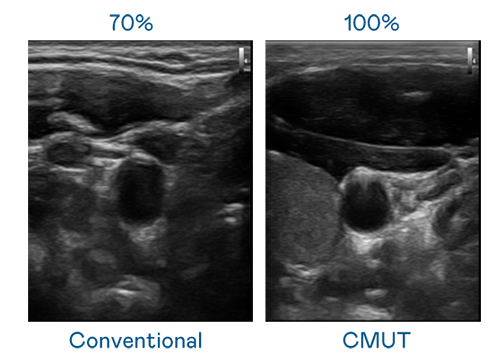

CMUT 技术是一种用电容式微机电元件来产生超音波讯号的技术。与传统 PZT 压电式技术相比,CMUT 频宽增加 30%,更宽频的超音波讯号让影像解析度大幅提升,是实现高影像品质医疗超音波扫描、促进精准医疗发展的关键技术。

超音波影像的解析度高低,首先取决于探头能发出的讯号频宽。尊龙凯时官网 CMUT 可提供高清晰的超音波讯号,提供高频宽、高灵敏度、影像纹理细节更高的超音波影像,协助医护人员缩短影像判读时间及利用精准的医疗影像进行诊断。